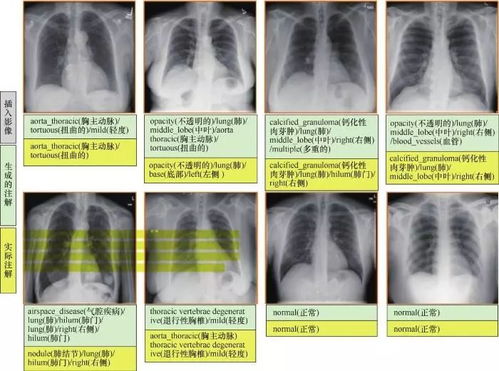

减少重复拍摄:过去,由于曝光不当导📝致影像质量不合格而需要重复拍摄的情况并不少见。100%曝光软件显著降低了重复拍摄的概率,不仅节约了宝贵的设备使用时间,也减少了患者的等待时间和不必要的辐射暴露。辅助AI影像分析:随着人工智能(AI)在医学影像领域的广泛应用,高质量、标准化的影像数据是AI算法进行有效分析的前提。

100%曝光软件生成的优质影像,为AI辅助诊断系统提供了更可靠的输入,能够更准确地识别病灶、量化指标,从而提高诊断效率和准确性。